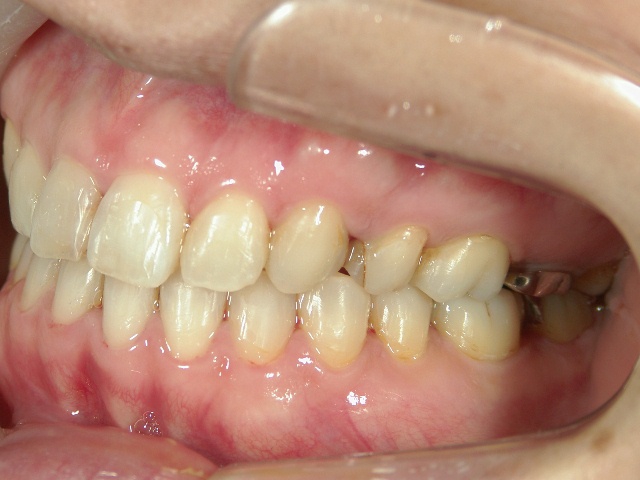

全顎ワイヤー矯正 症例(2)

36歳女性 磐田市

在住

治療期間2年6

ヶ月